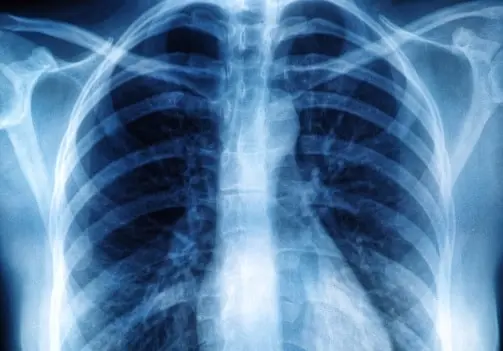

O diagnóstico é feito por meio de exames como prova de função pulmonar (espirometria) e exames de sangue/Foto: Reprodução

O diagnóstico é feito por meio de exames como prova de função pulmonar (espirometria) e exames de sangue. “Temos algumas drogas que podem retardar o processo dessa doença, mas são altamente caras, na faixa de dez a treze mil reais. É um tratamento caro, mas possível,” comentou Dra. Célia.